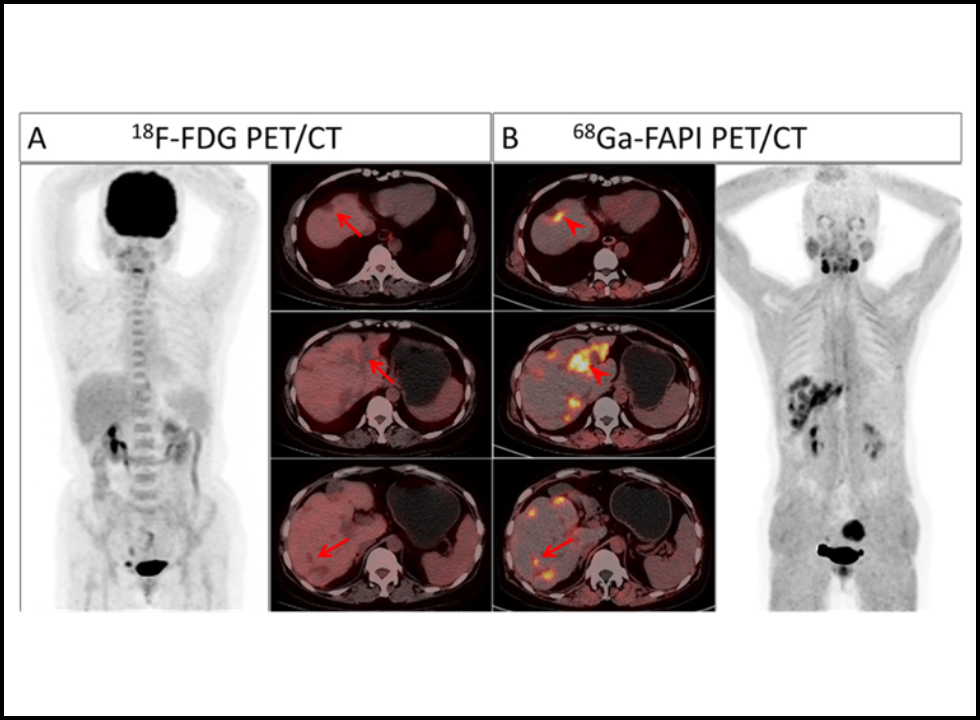

Most cases pop up incidentally during imaging for something else: a neck CT scan ordered after a car accident, a routine ultrasound for a thyroid nodule check, or even a PETCT done while looking for another cancer. A study in JAMA Otolaryngology (2022) found that nearly 30% of newly diagnosed papillary cancers were found this way.